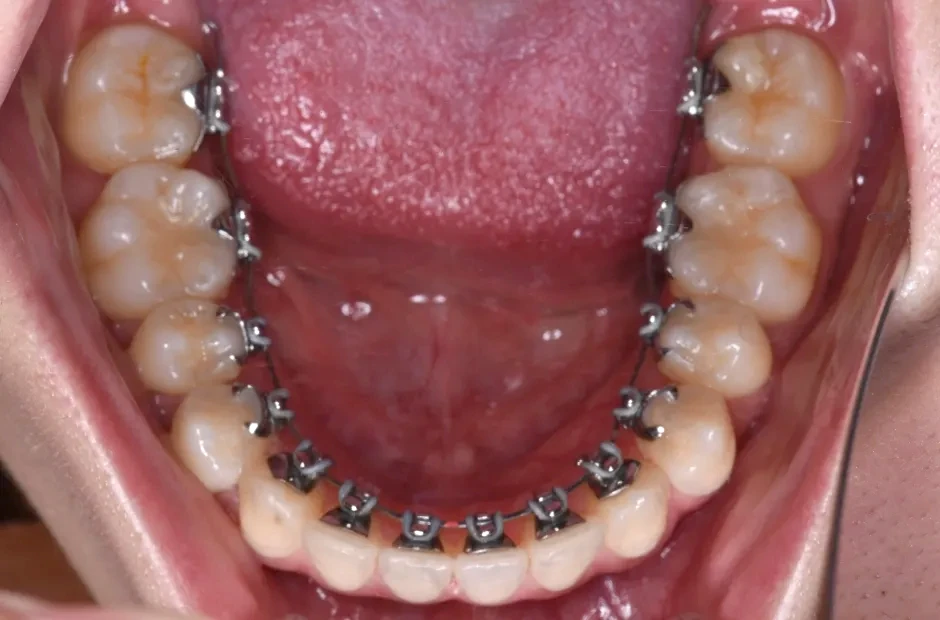

叢生

| 診断名・主訴 | 叢生 |

|---|---|

| 年齢・性別 | 43歳・女性 |

| 治療期間・回数 | 2年7か月 27回 |

| 治療に用いた主な装置 | 舌側矯正 |

| 抜歯部位 | 両顎4,4 |

| 治療費 | 100万円(税抜) |

| リスク・副作用 | 装置による違和感・疼痛・歯肉退縮・歯根吸収・虫歯のリスクなど |

治療中